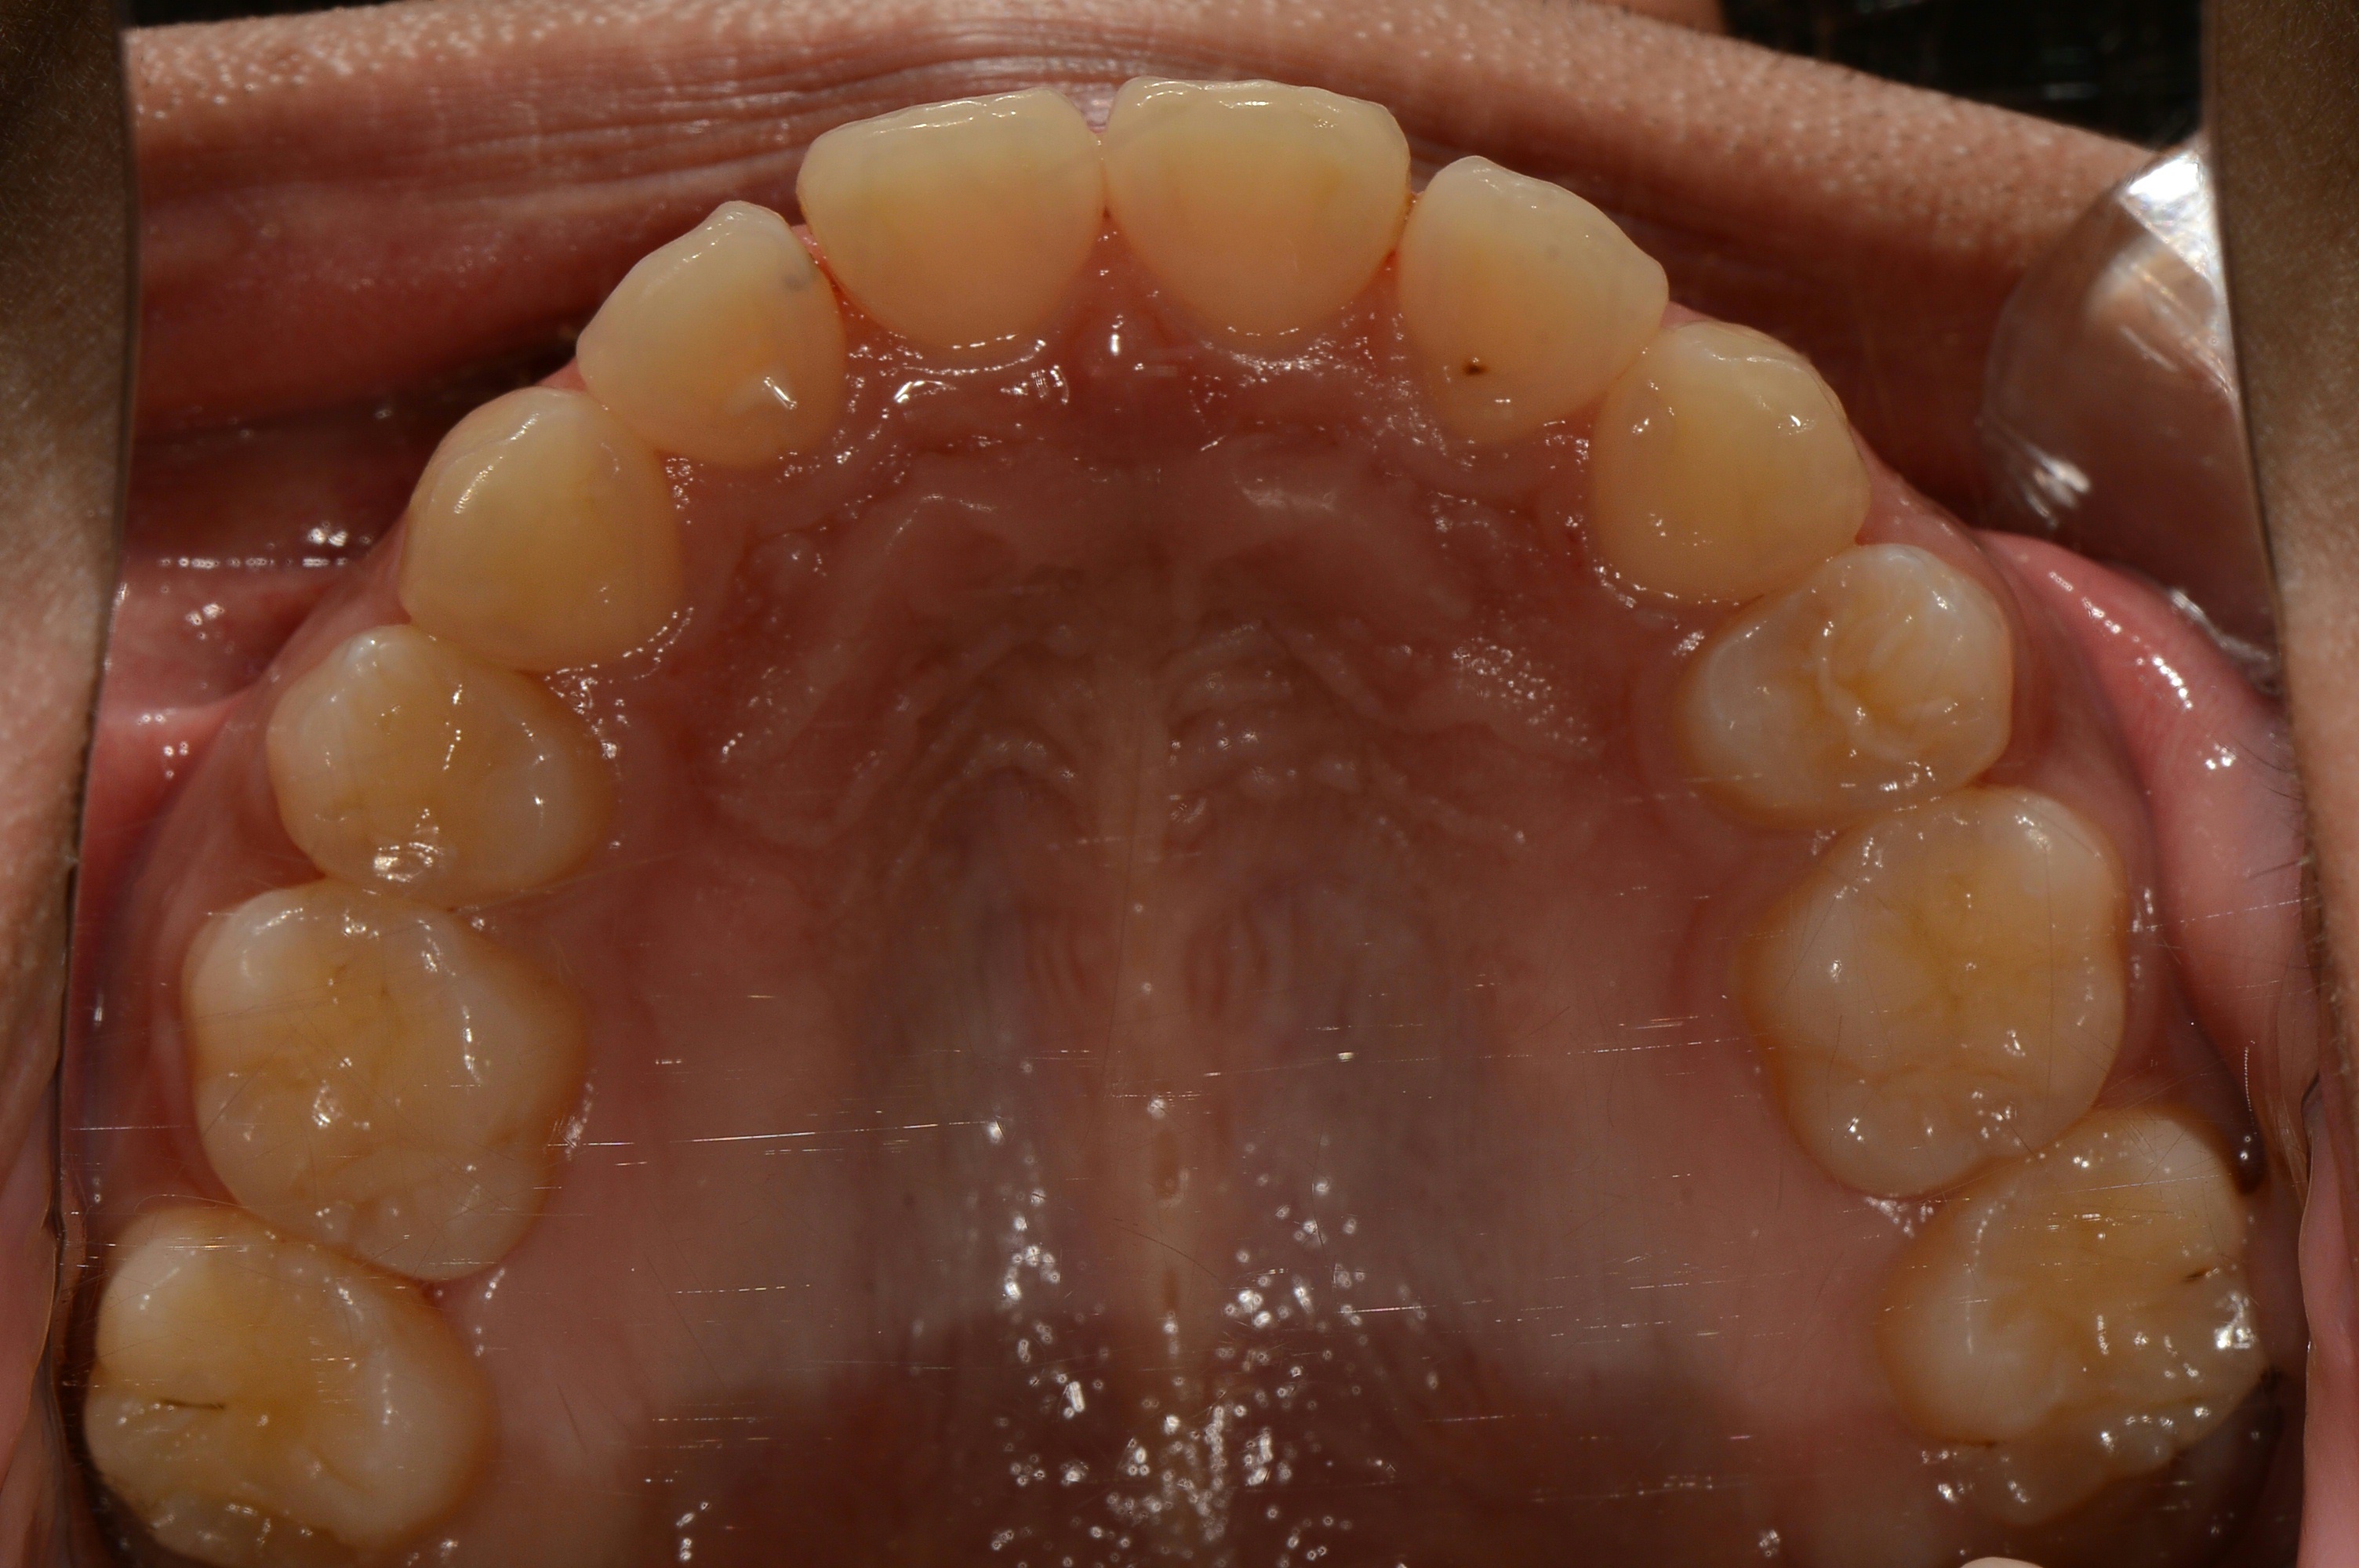

치료 후 사진입니다.